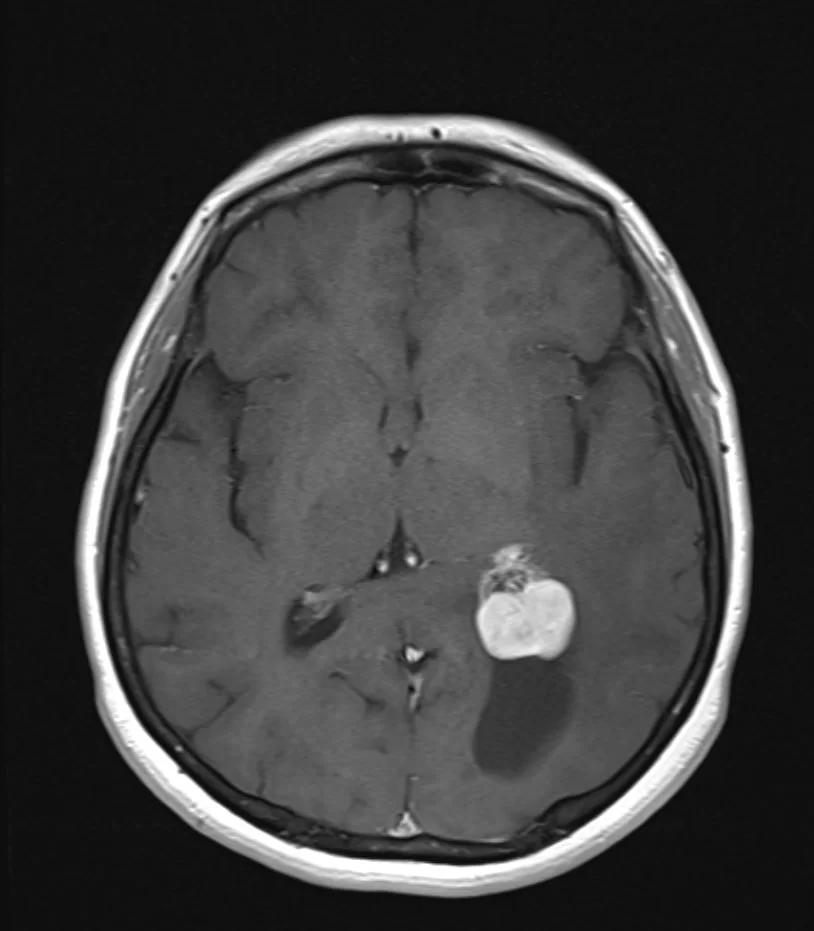

Η μαγνητική τομογραφία ανέδειξε χωροκατακτητική εξεργασία εντός της αριστερής πλάγιας κοιλίας του εγκεφάλου.

Το συγκεκριμένο ενδοκοιλιακό μηνιγγίωμα παρουσιάζει δύο πλεονεκτήματα για τον νευροχειρουργό. Πρώτον, είναι σχετικά μικρό σε μέγεθος και δεύτερον έχει μια κύστη η οποία δημιουργεί «χώρο» τον οποίο μπορεί να εκμεταλλευτεί ο νευροχειρουργός.